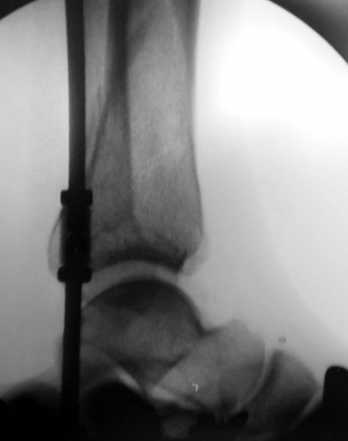

Глубокоуважаемые коллеги! Необходима ваша помощь.На консультацию обратился пациент 27 лет.

1,5 месяца назад при падении со скалы получил перелом пилона, лечился в районной больнице консервативно (циркулярная гипсовая повязка до средней 1/3 бедра). К нам попал только сегодня, сделали снимки и возник вопрос - делать ли что-то хирургически или уже пойти только на восстановительное лечение (продолжить иммобилизацию еще на 2-4 недели, потом разработка движений и т.п.)?Снимки прилагаю.

Уважаемые коллеги! Внутрисуставной перелом дистального конца б/б кости со смещением и подвывихом стопы должен был лечиться оперативно в раннем сроке.

По поводу обсуждаемого случая - 6-недельная фиксация такого перелома значительно увеличила шансы на артроз голеностопного сустава. Дальнейшая фиксация в гипсе практически сравняет эти шансы со 100%.